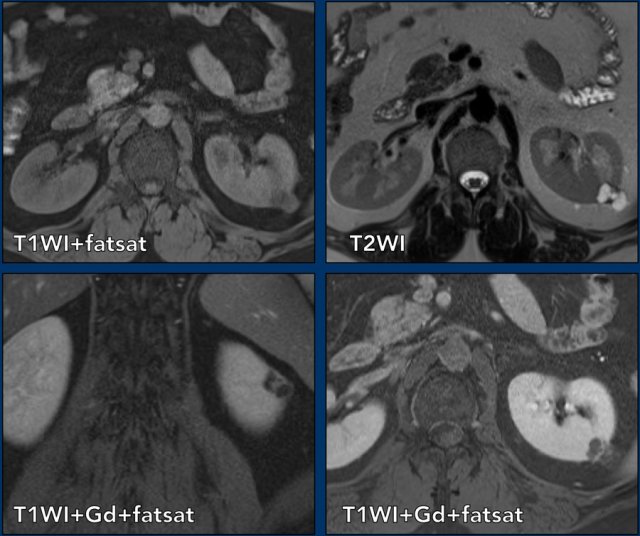

case 2

There is a cystic mass in the right kidney with many (> 4) smooth thin enhancing septa.

The lesion is classified as Bosniak IIF.